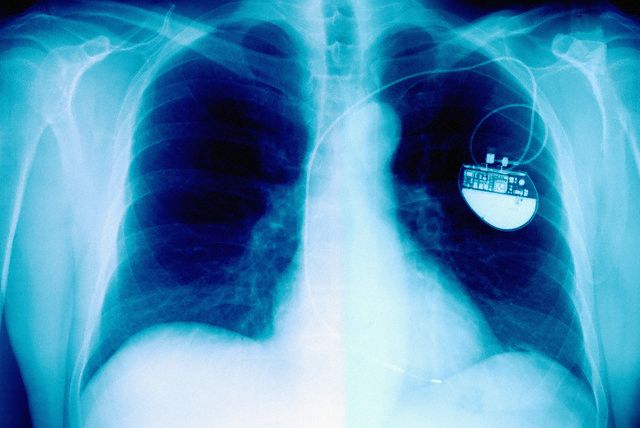

Обычный проводной кардиостимулятор на рентгеновском снимке. (Фото Charles O'Rear / Corbis.)

Хотя электрокардиостимуляторы спасают множество жизней – по статистике, более 3 млн людей по всему миру носят в себе такие устройства – их использование сопряжено с определёнными неудобствами. Электрокардиостимулятор, или искусственный водитель ритма, помогает восстановить нормальную частоту и периодичность сердечных сокращений – в противном случае расстройства ритма могут привести к довольно тяжёлым последствиям для всего организма, вплоть до смерти. Но для того, чтобы водитель ритма заработал, его электроды нужно вживить в сердце, провода от них подключить к генератору импульсов, который вживляют под кожу.

Со временем кардиостимуляторы становились всё меньше, а электроды с проводками стало возможным вводить в сердце с помощью катетера просто через вены. Однако каким бы маленьким ни был стимулятор и какими бы тонкими ни были его провода, ему всё равно нужно менять батарейки, а это означает неизбежную операцию, пусть и небольшую. Кроме того, проводки с электродами, тянущиеся к сердцу, могут изнашиваться, и время от времени их тоже нужно менять. С другой стороны, из-за необходимости тянуть провода мы не можем поставить стимулятор, куда вздумается, и не можем использовать много точек для стимуляции. Самому сердцу не всегда «нравится», что его стимулируют внешним устройством. Наконец, если речь идёт о детях, то им не всегда вообще можно поставить искусственный водитель ритма.